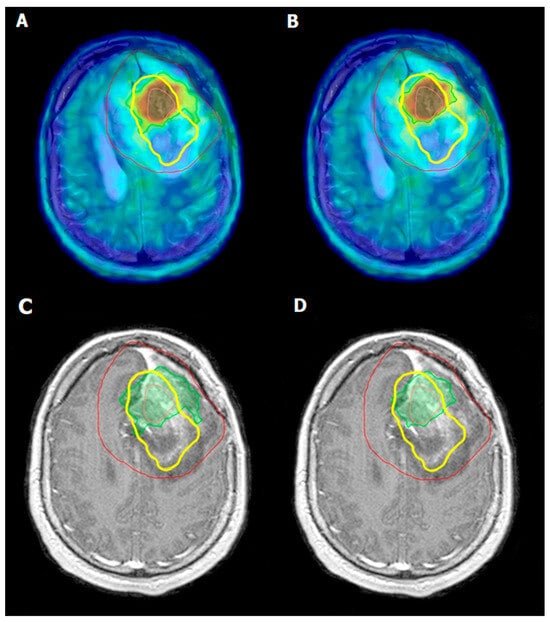

The efficacy of 18F-FDOPA PET in monitoring tumor response to radiotherapy in GBM patients has shown promising results, particularly in distinguishing between a tumor recurrence and radiation necrosis. Specifically, 18F-FDOPA PET has been shown to have a sensitivity ranging from 81% to 96%, and a specificity ranging from 77% to 100% in distinguishing between a tumor recurrence and radiation necrosis [42,52]. Post-radiotherapy, conventional imaging modalities like MRI often face challenges in differentiating treatment-related changes from tumor regrowth due to overlapping radiographic features. 18F-FDOPA PET addresses this limitation by exploiting the differential metabolic activity between viable tumor cells and necrotic tissue. Tumor cells exhibit increased amino acid transport and the uptake of 18F-FDOPA, resulting in higher PET signal intensities; whereas, radiation necrosis, characterized by non-viable tissue, shows reduced or absent tracer uptake [52,53]. Studies have demonstrated that 18F-FDOPA PET can reliably detect metabolic changes in GBM with a sensitivity and specificity that often surpass those of MRI alone. Furthermore, a quantitative analysis of 18F-FDOPA uptake allows for the assessment of metabolic response to radiotherapy over time, providing valuable prognostic information and aiding in the optimization of treatment plans (Figure 2) [52,53,54,55].

Figure 2. Left frontal post craniotomy status. Inhomogeneous, mainly centrally, moderate enhancement of contrast material is observed on T1-weighted post-contrast MRI images. The lesion in the left hemisphere is surrounded by edema (C,D). Irregularly shaped intense, focal 18F-FDOPA accumulation can be detected on the left side of the brain frontally, above the level of lateral ventricles (A,B). Pink line—GTV, green line—BTV 1.7 (A,C), green line—BTV 2.0 (B,D), red line—PTV, and yellow line—recurrence [42].